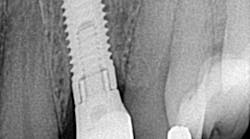

CAN YOU REALLY IDENTIFY more than 900 dental implants by looking at a single radiograph? I got my answer to this question when a patient came in and needed his lower fixed hybrid prosthesis removed. That bad boy had been on there for a long time and was, quite frankly, nasty! The problem? There was no record of who placed the implants or which dental implant system was in place. What did I do? Well, what do others do when they are faced with the same dilemma? You can read about it at this link; you may be surprised at just how much information a single radiograph can give you!